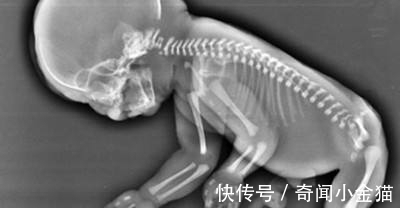

一听美人鱼综合症就知道,此病一定与美人鱼有关,患此病的人看起来和传说中的美人鱼差不多,两腿的内侧沾粘在一起,就像鱼的尾巴一样,几年前一对国外的年轻夫妇就生下这样的一个婴儿,一生下来双腿就长在了一起,脚掌成外八字,像极了美人鱼,一时引起了很大的轰动。

医生表示,这个美人鱼综合征的典型特征,婴儿患上这种疾病的概率为七万分之一,在父母的坚持和医护人员的努力下,这位女孩竟然奇迹般的活了下来,经过仔细的检查发现,她的一些重要器官都在慢慢的发育,只是不能达到正常人的水准,由于双脚的不便,让她无法像其他正常人一样活动自如,缺乏运动的小美人鱼如今以然成为了一个“小胖墩”,父母也表示希望能够多带她去看看外面的世界,将来以一个健康的心态和身体去接受手术迎接正常人的生活。